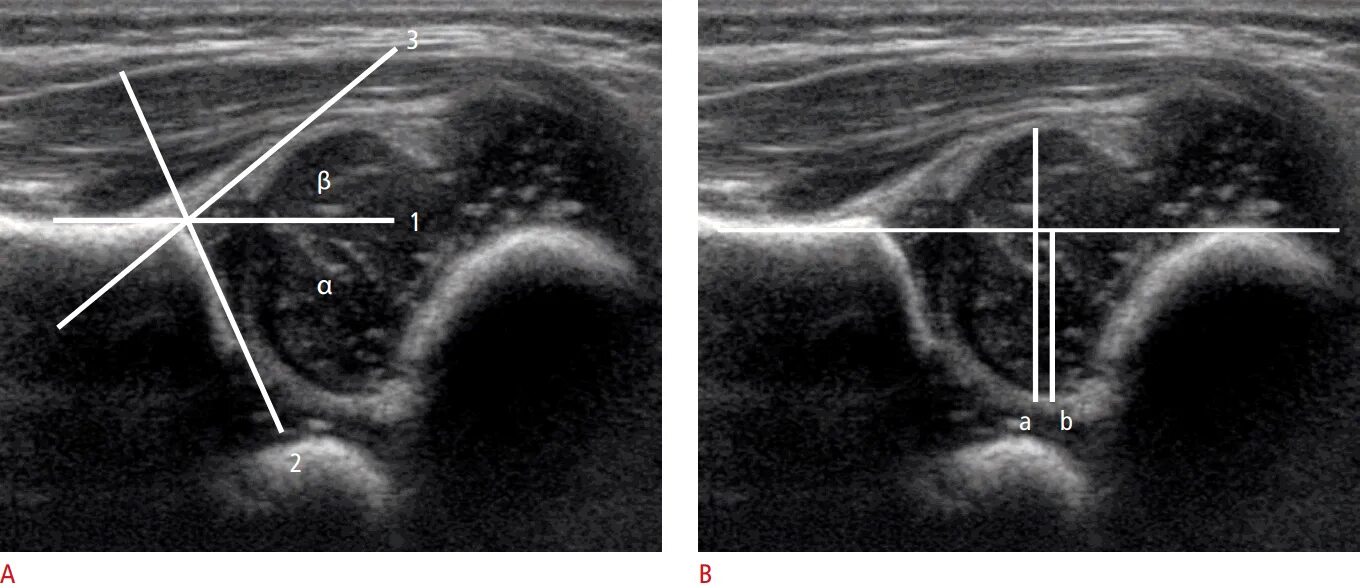

Где сделать узи тазобедренного сустава